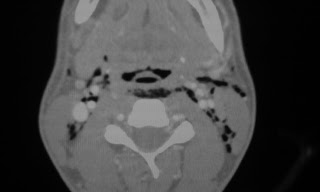

Pneumomediastinum and surgical emphysema.